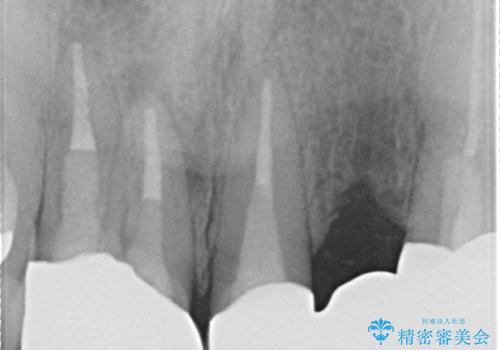

- 昔入れた被せ物と歯茎の間の隙間が気になると来院された方の症例です。

右上1、2番目の歯と左上1、2、3、番目の歯のブリッジを除去し、オールセラミッククラウンによる補綴を行うことで見た目を改善しました。

根管治療の注意事項(リスク・副作用など)

- 根管治療により類似の全ての症例の問題が解決するわけではなく、症例はあくまでも一例です

- 根管治療により痛みや腫れがひかない事や、術後に痛みや腫れが生じる事、治療によるファイル破折やパーフォレーションなどの偶発症、術後の歯根破折を生じる可能性もあります